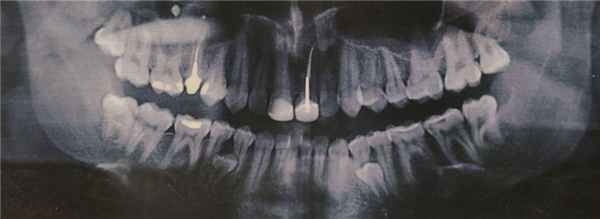

Окончательный ответ при подозрении на ретенцию могут дать рентгенологические методы исследования [4]. Это, прежде всего, прицельные снимки. Одиночный снимок может дать врачу двухмерное представление о зубе. Врач может оценить положение зуба в вертикальной плоскости и в мезиодистальном направлении.

Более информативно изучение ортопантомограммы. Данный вид исследования дает информацию о положении ретинированного зуба в мезиодистальном направлении, однако не всегда можно точно выявить сложную анатомию его взаиморасположения с соседними зубами. Современный метод трехмерной дентальной компьютерной томографии позволяет точно определить расположение ретинированного зуба в трех взаимно перпендикулярных плоскостях и его соотношение с соседними анатомическими структурами, что помогает в планировании операции.

Рис. 1. Последствия травмы корня зуба 1.1 при удалении сверхкомплектного зуба в возрасте 8 лет

Рис. 2. Деформация и патологическая резорбция корня зуба 1.1 на рентгенограмме

В 16 лет я увидел панорамный снимок на фото выше и, уже успев натерпеться стоматологии и врачей, я загрустил (я только что сильно болел фронтитом и гайморитом в 15 лет, в 7 классе только перестав носить пластинку, я побежал, споткнулся и выбил передние зубы о бетонную плиту). Я спросил врача в Красноярске, который анализировал снимок, мол что же делать с лишними зубами (а тогда они еще не особо мешали и только слегка прощупывались)? Я получил довольно точный ответ в духе - нужно надрезать десну, отворачивать ее, сверлить кость и удалять зубы. Это меня впечатлило настолько, что я отложил решение этого вопроса аж до 29 лет. Да и не до этого как-то было.